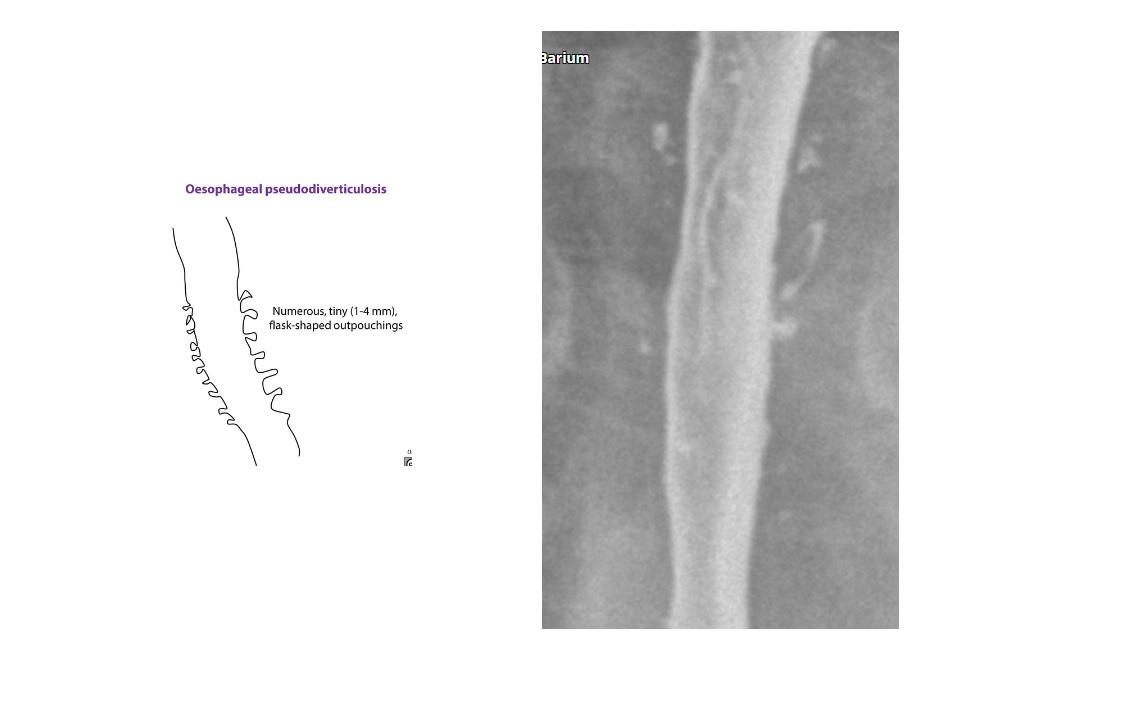

Oesophageal pseudodiverticulosis

Barium - multiple, tiny (1- to 4-mm depth), flask-like outpouchings in the oesophagus

Barium trapped in dilated excretory ducts of submucosal glands

CHRONIC REFLUX* and Candida